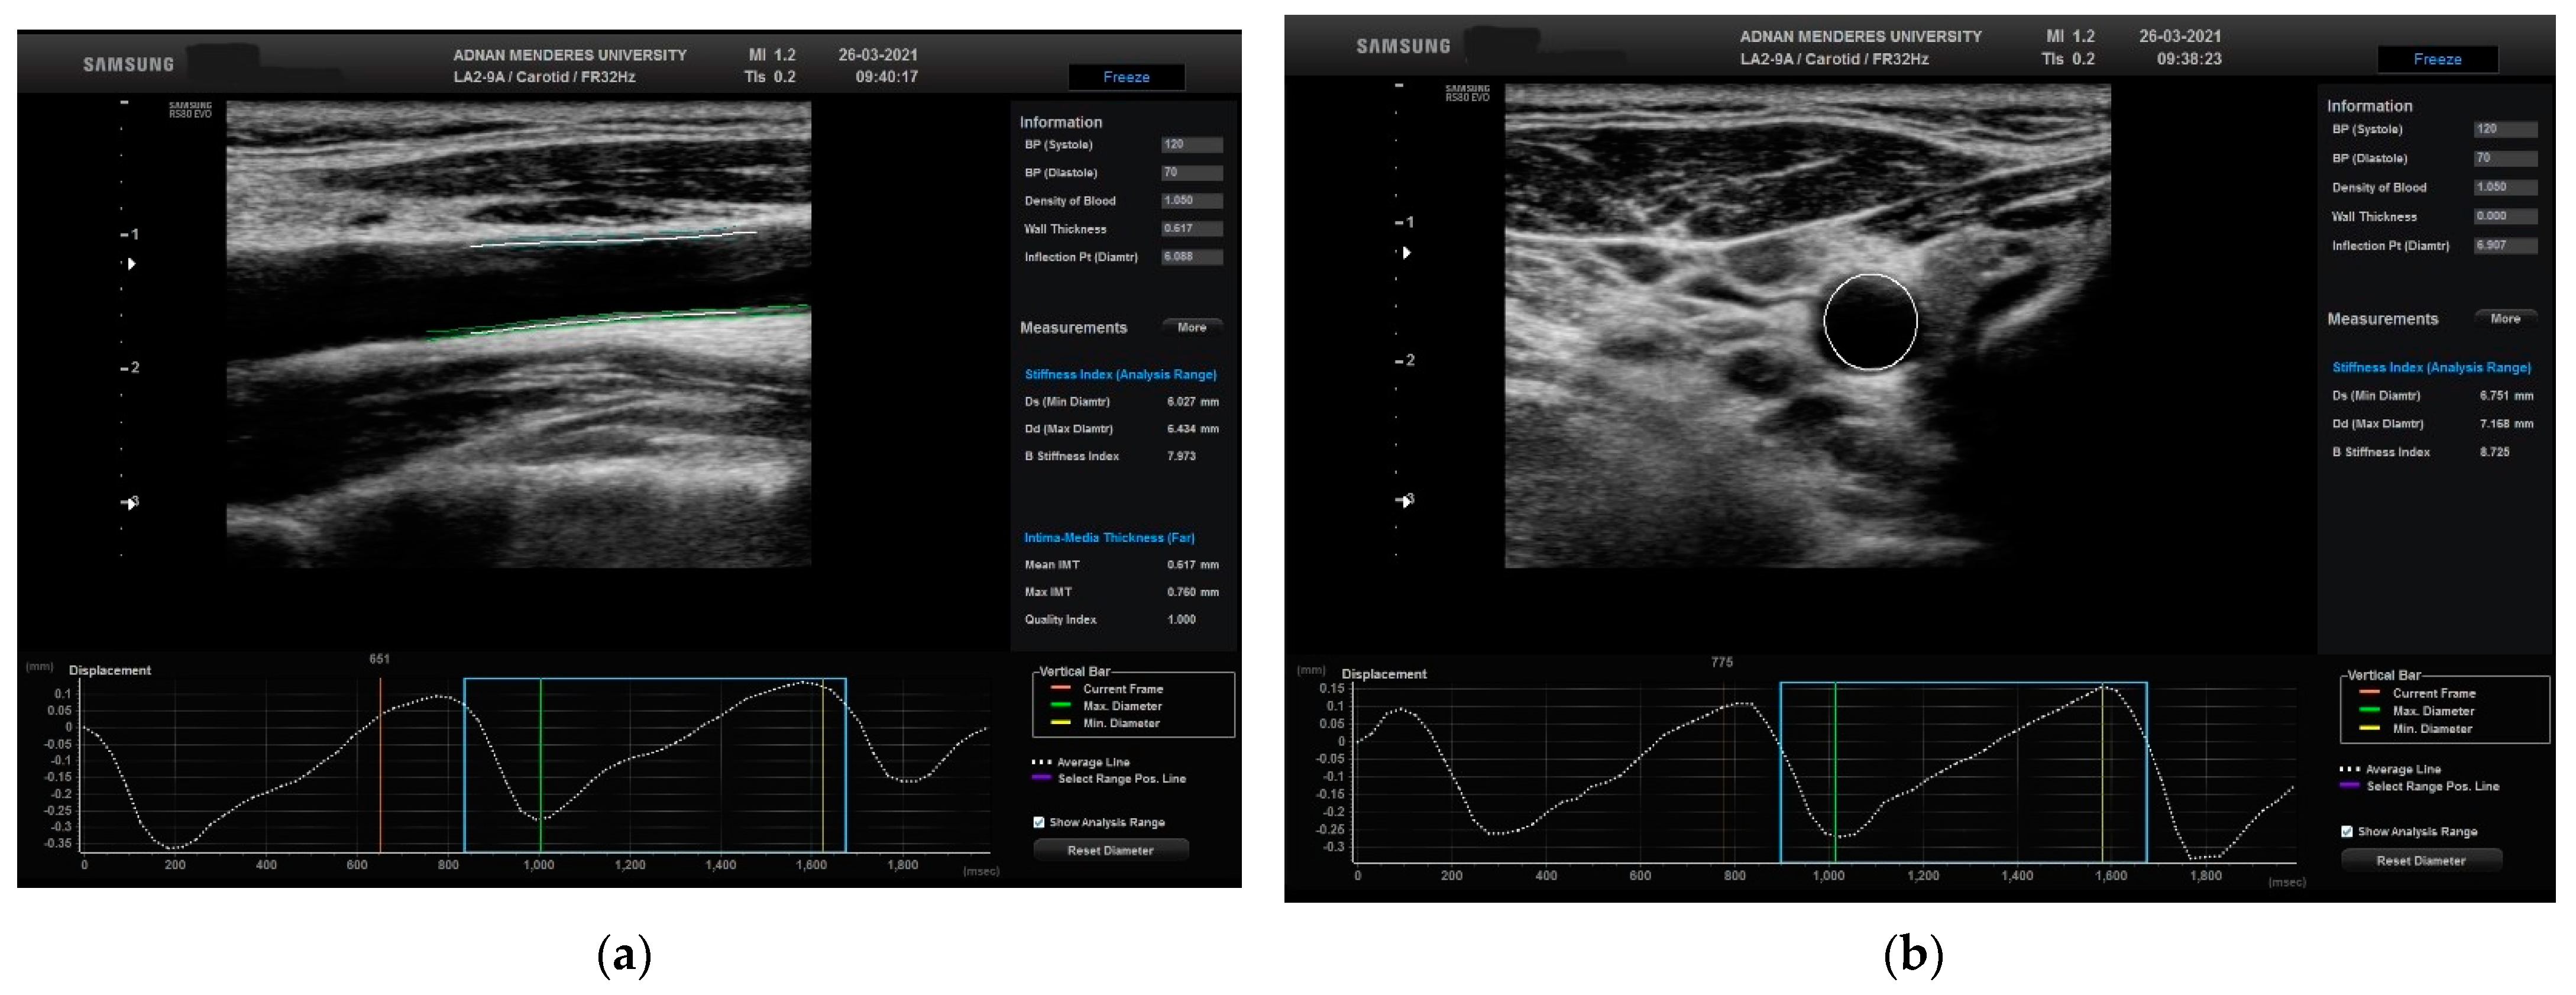

2.2. Speckle Tracking Carotid Strain Analysis (STCS)